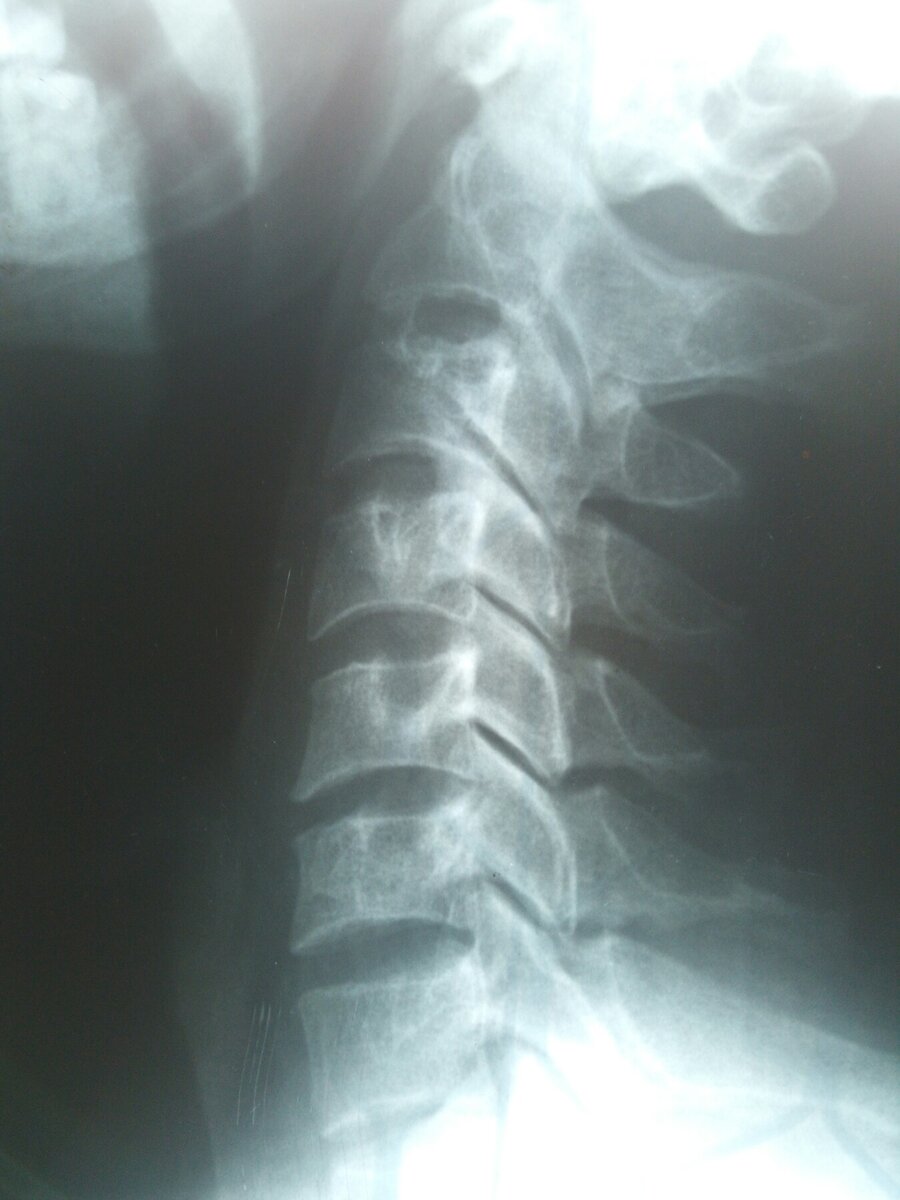

Межпозвонковая грыжа является одним из тяжелейших заболеваний. Она может лишить человека трудоспособности на длительное время. В некоторых случаях требуется даже стационарное лечение. И несмотря на принимаемые меры межпозвонковая грыжа остаётся на всю жизнь. Поэтому важно научиться жить с ней так, чтобы не вспоминать о её наличии.

Перечислю некоторые моменты, которые могут "разбудить спящую" грыжу.